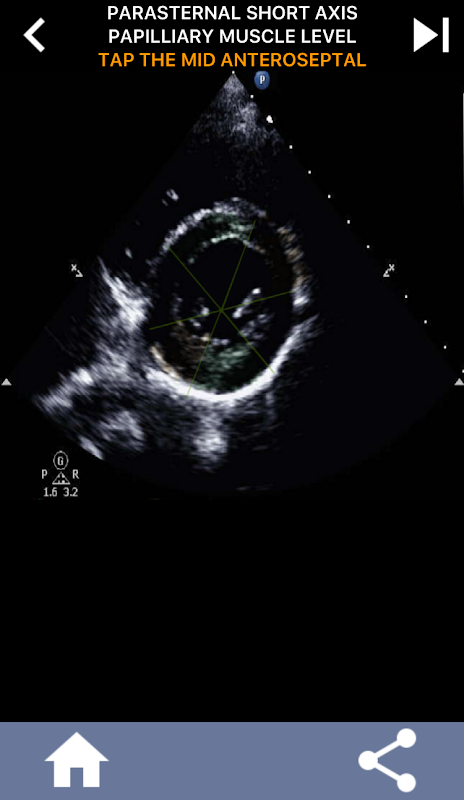

AHA 심장 세그먼트 학습을 위한 퀴즈 기반의 시각적 접근 방식: 심초음파

AHA(미국 심장 협회) 심장 세그먼트를 이해하는 것은 심장 초음파 기사가 보고서를 작성하는 심장 전문의와 효과적으로 의사 소통하는 데 가장 중요합니다. 특정 해부학적 부위와 해당 부분을 알면 소노그래퍼는 모든 이상 또는 발견 사항을 정확하게 설명하고 전달할 수 있으므로 두 전문가 간의 명확하고 간결한 커뮤니케이션이 보장됩니다.

이 앱은 실제 에코 이미지를 사용하여 여러분의 지식을 테스트할 것입니다. 저는 종종 이것이 최고의 교육 방법이라고 생각합니다.